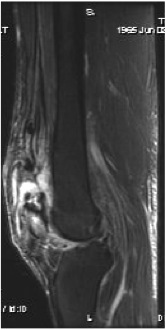

MRI